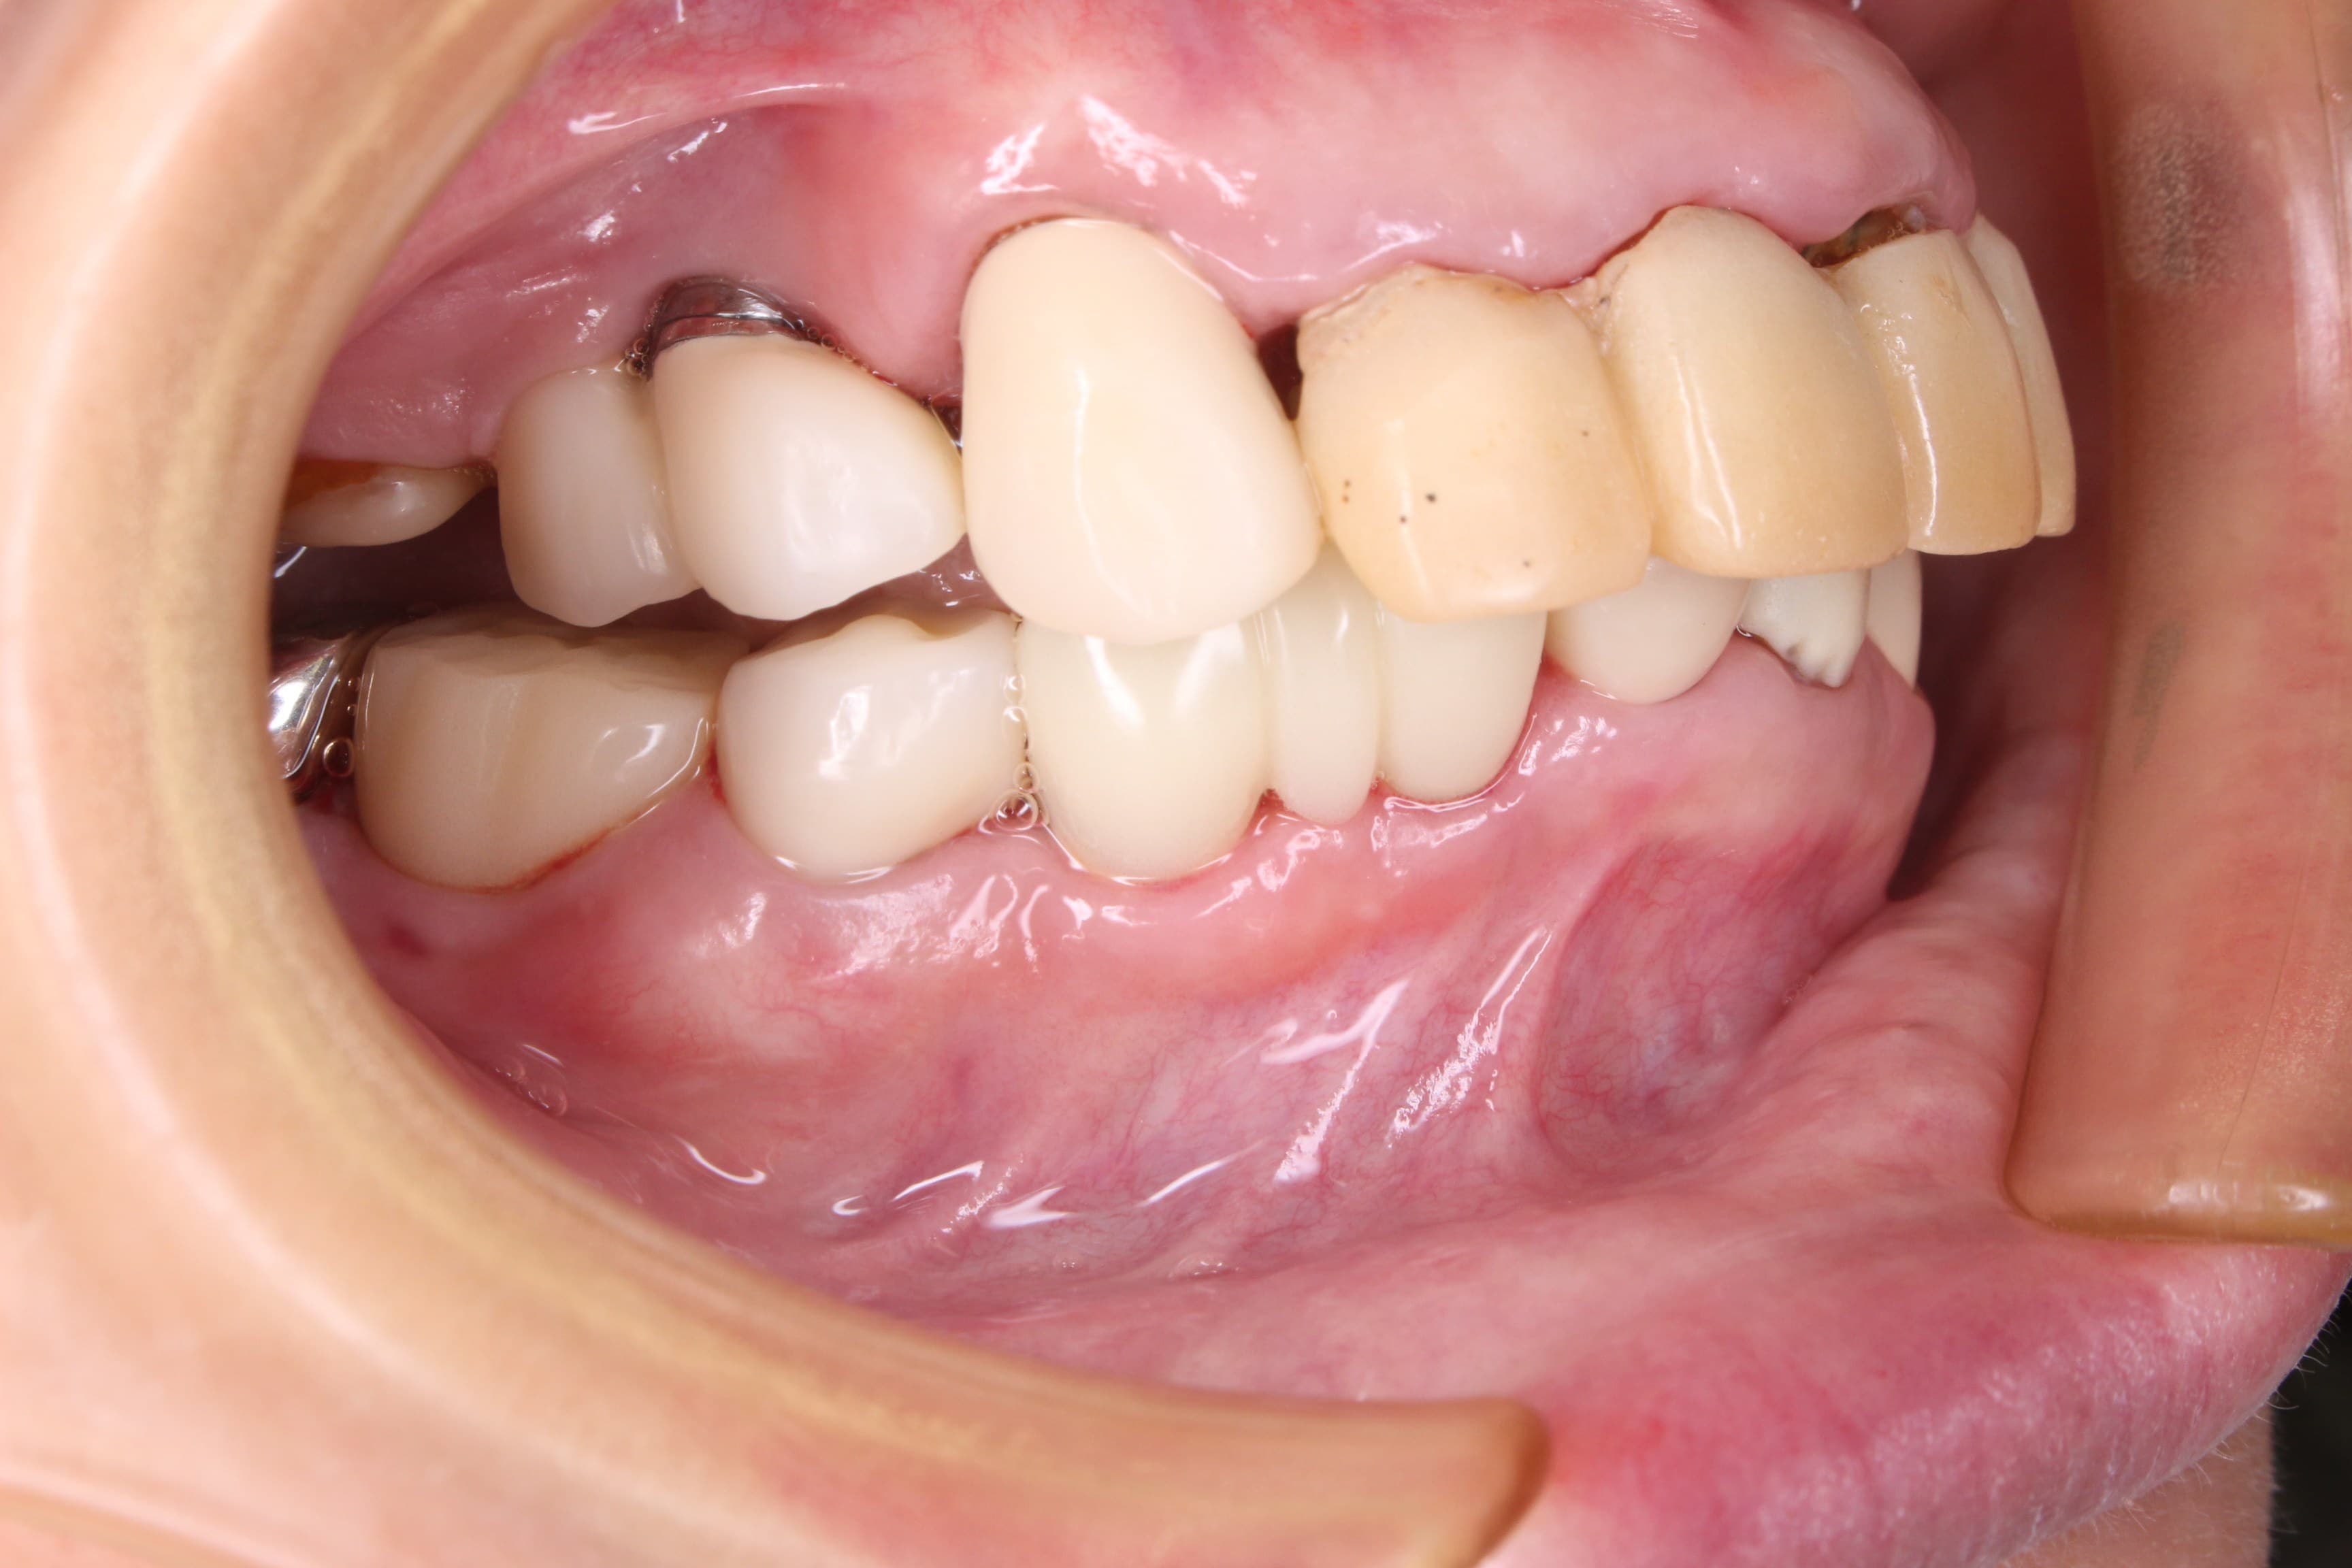

下の写真は、上記の内容を説明し4週間程経過した状態を記録したものです。

写真の様に炎症はかなり改善されてきています。

見違える程綺麗にお手入れして頂けているおかげです。